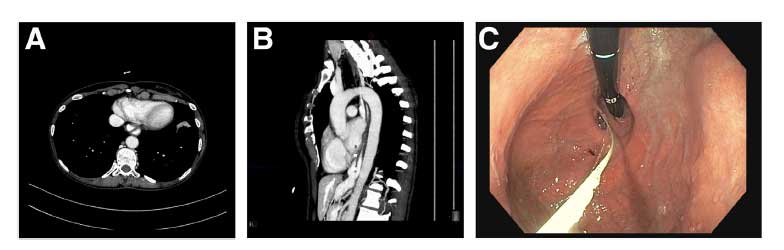

QUIZ: Um esôfago de aparência incomum